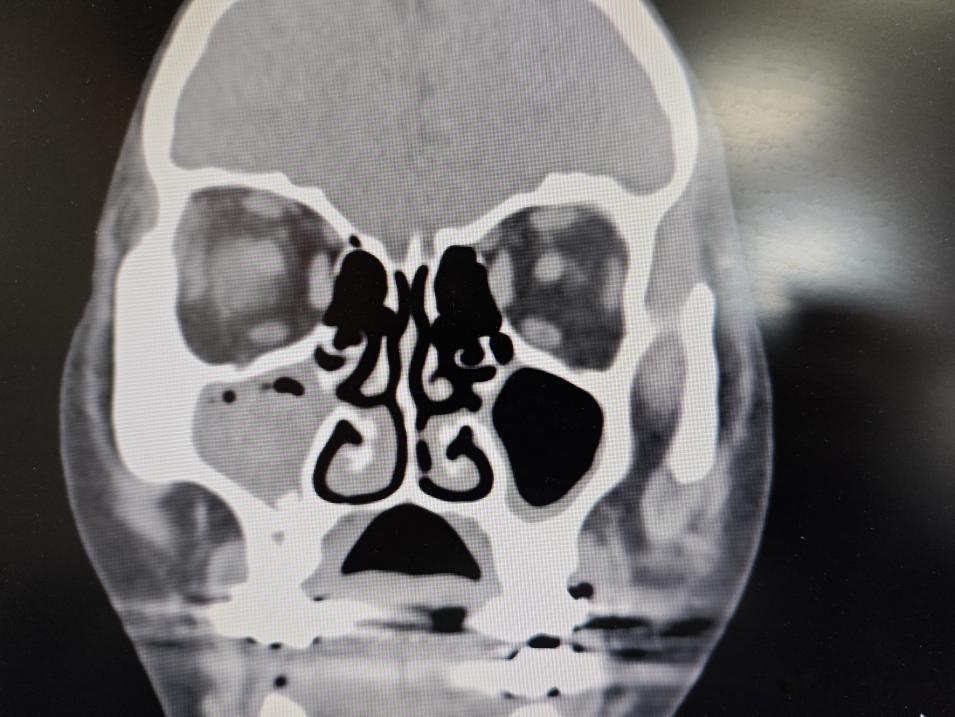

先跟大家说说这两位大姐的情况,说不定你身边也有这样的人。第一位大姐,平时总说头昏痛,擤鼻涕还偶尔带血,一开始以为是高血压引起的,自己吃了点止痛药、降压药,扛了大半年,直到最近头痛得睡不着、鼻涕里血丝越来越多,才来检查,一查就是真菌性鼻窦炎,鼻窦里都长满了“霉块”。

第二位更让人意外,她一开始是眼睛不舒服,流泪、红肿,去眼科查是阻塞性泪囊炎,本以为只是眼睛的问题,做了CT才发现,罪魁祸首居然是鼻窦里的真菌——真菌感染堵塞了泪囊通道,才引发了眼疾。这也印证了我之前在微信公众号、头条账号里反复说的:鼻窦出问题,不止是鼻子难受,还可能牵连眼睛、头部!

它主要分两种:一种是非侵袭性的,最常见,真菌只待在鼻窦里,不破坏骨头和黏膜,及时治疗预后很好;另一种是侵袭性的,虽然少见,但特别凶险,真菌会侵蚀骨头,还可能蔓延到大脑、眼眶,危及生命。

临床表现也不一样,有的像第一位大姐,头昏痛、涕中带血;有的鼻塞、流脓涕,有臭味;还有的像第二位大姐,牵连眼睛出问题。大家要是有这些症状,别硬扛,赶紧去检查。